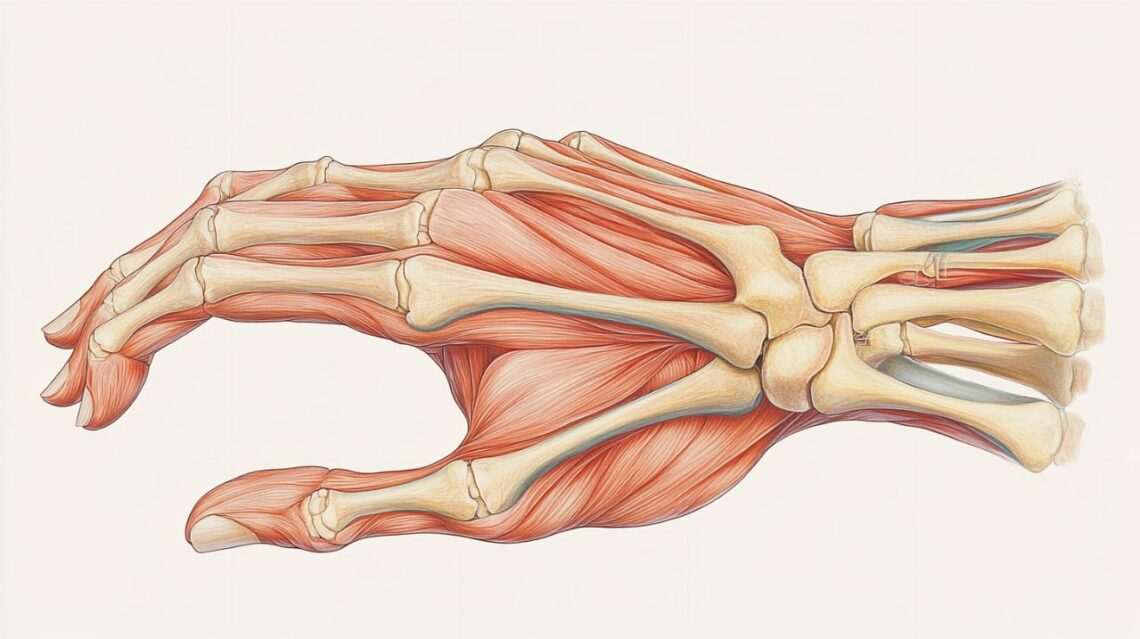

La déformation en boutonnière survient lorsque le tendon extenseur, plus précisément la bandelette centrale de l'extenseur, subit une rupture tendineuse au niveau de l'articulation interphalangienne proximale. Cette lésion provoque un déséquilibre biomécanique qui entraîne progressivement une posture anormale du doigt. L'articulation interphalangienne proximale adopte une position en flexion tandis que l'articulation interphalangienne distale bascule en hyperextension, créant ainsi l'apparence caractéristique qui donne son nom à cette pathologie.

Au-delà des blessures aiguës, certaines pathologies chroniques favorisent cette déformation. La polyarthrite rhumatoïde figure parmi les causes médicales principales, l'inflammation articulaire fragilisant progressivement les structures tendineuses. L'arthrose peut également contribuer à l'apparition de cette condition, notamment chez les patients présentant une usure articulaire avancée. Dans tous les cas, la rupture de la bandelette centrale entraîne une redistribution anormale des forces au sein du système extenseur, expliquant la déformation progressive qui s'installe en quelques semaines en l'absence de traitement orthopédique approprié.